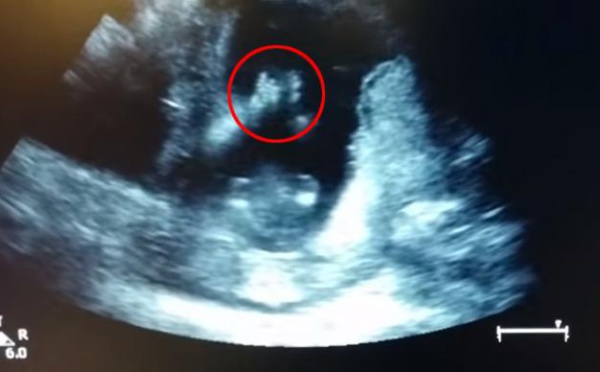

Un bébé applaudit... dans le ventre de sa mère

Ce futur bébé sera-t-il un vrai boute-en-train? Il semble en tout cas avoir des prédispositions à l'enthousiasme. Lors de l'échographie de la quatorzième semaine de grossesse, on peut l'apercevoir applaudir dans le ventre de sa mère.  Le voyant taper dans ses mains, la maman a décidé de l'encourager. "J'ai chanté une...